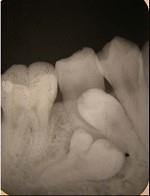

融合牙是 ( ) A.仅见于恒牙 B.两牙牙骨质相连 C.仅见于乳牙 D.两牙牙本质相连 E.两牙牙釉质相连

选项 A.仅见于恒牙 B.两牙牙骨质相连 C.仅见于乳牙 D.两牙牙本质相连 E.两牙牙釉质相连

答案 D